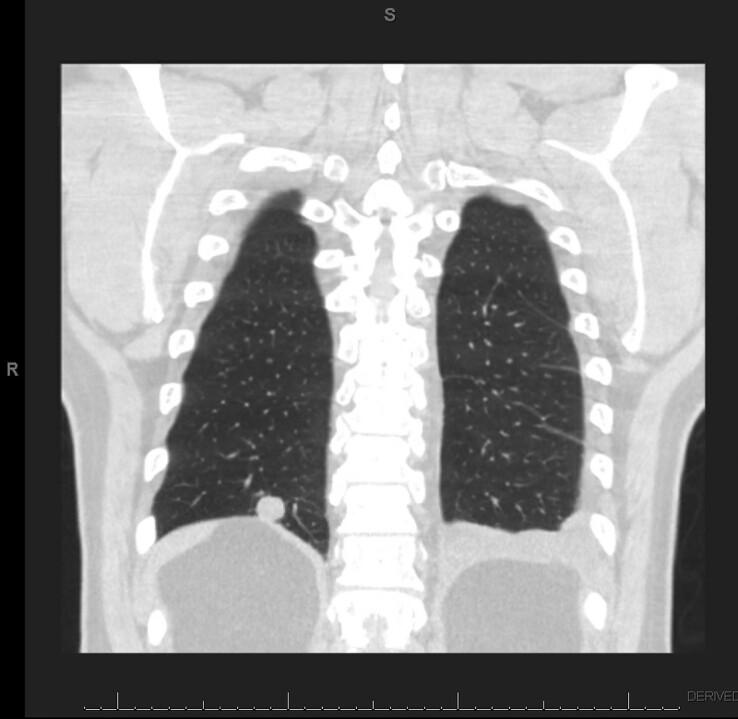

A male patient with distant history of extensive rabbit contact and pulmonary nodules for 6 years developed empyema. Francisella tularensis holarctica was isolated from thoracentesis fluid. Retrospective immunohistochemical examination of a pulmonary nodule, biopsied 3 years prior, was immunoreactive for F. tularensis. These findings suggest the potential for chronic tularemia.